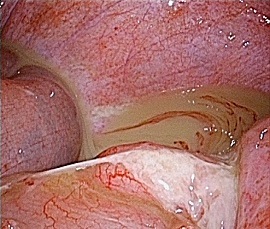

[急性虫垂炎] 手術:腹腔鏡下虫垂切除術(虫垂周囲膿瘍を伴う)

急性腹症のため救急受診。精査の結果、急性虫垂炎と診断。緊急手術(虫垂周囲膿瘍を伴う腹腔鏡下虫垂切除術)を施行した。病理診断結果は急性化膿性虫垂炎であった。

手術画像